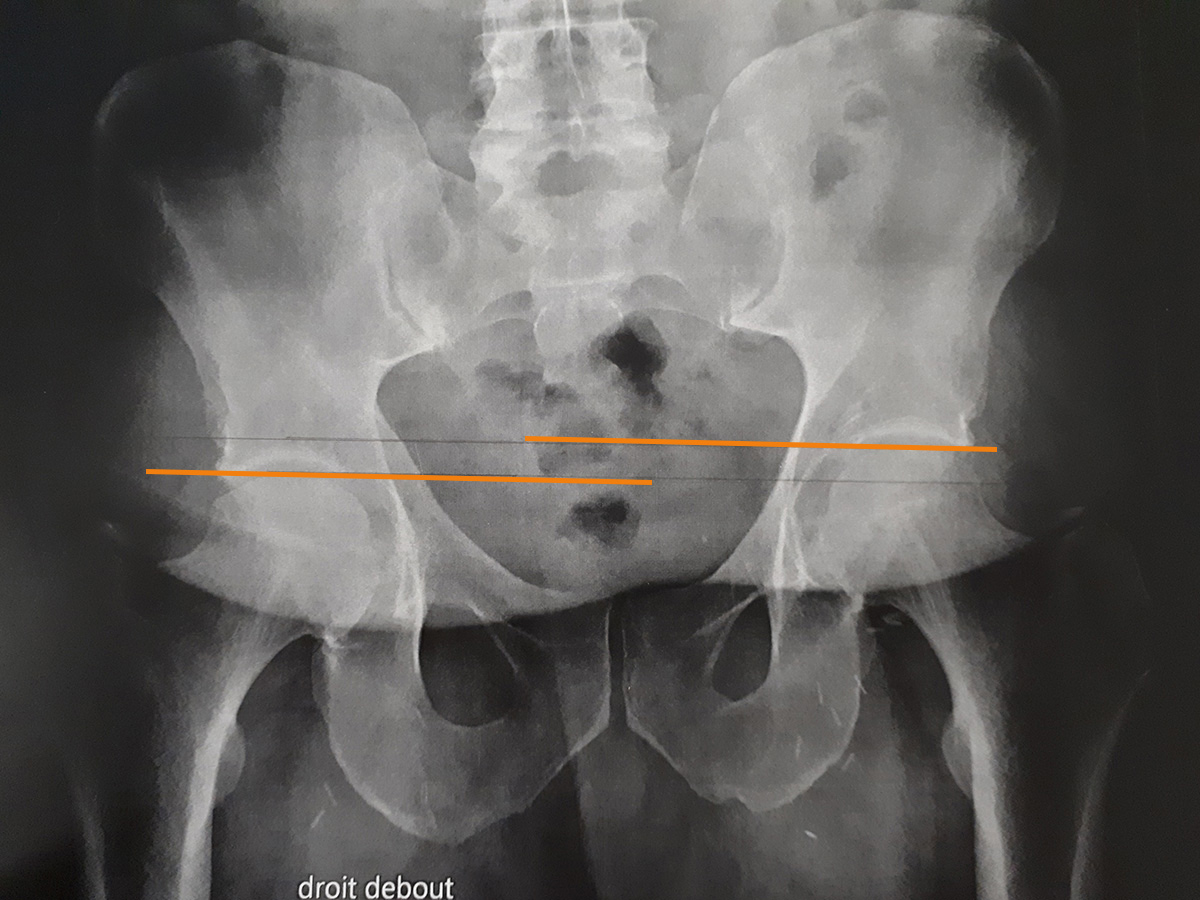

Inégalité de longueur des membres

L'inégalité de longueur des membres inférieurs est en rapport avec une asymétrie de longueur d'un ou plusieurs des os des membres inférieurs (fémur, tibia).

Cette pathologie est à distinguer d'une asymétrie d'alignement (fausse inégalité de longueur des membres inférieurs), cas où il n'y a pas de différence de longueur, mais où il existe un déjettement du bassin secondaire à une hypertonicité de la musculature du pelvis ou d'un membre.